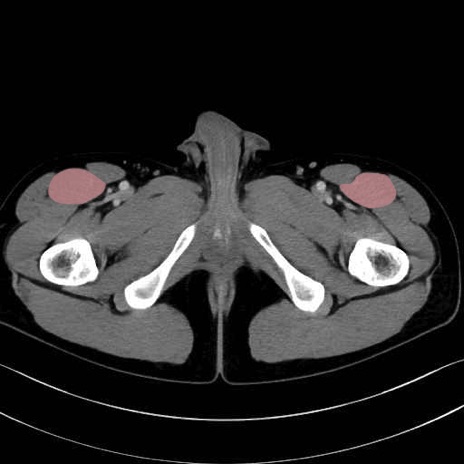

3. 殿部の筋肉(表層・中層・深層)

大殿筋 (Gluteus maximus)

中殿筋 (Gluteus medius)

小殿筋 (Gluteus minimus)

大腿筋膜張筋 (Tensor fasciae latae)

4. 深層外旋六筋(股関節の深部)

梨状筋 (Piriformis)